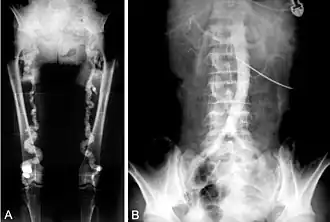

![]() B. Translumbar aortography shows near-total obstruction of the femoral arteries in a patient with Monckeberg's arteriosclerosis. | |